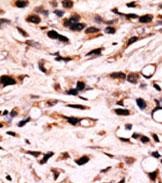

IHC 1/100-1/500 Human,Mouse,Rat

The Phospho-SMAD4 (T277) antibody is a specialized tool used to detect SMAD4 protein phosphorylated at threonine 277. a post-translational modification critical in regulating SMAD4 activity within the TGF-β signaling pathway. SMAD4. a central mediator of TGF-β signaling, functions as a tumor suppressor by facilitating the translocation of SMAD complexes into the nucleus to regulate target gene expression. Phosphorylation at T277 has been implicated in modulating SMAD4’s subcellular localization, stability, and interaction with co-regulators, thereby influencing its role in cell proliferation, differentiation, and apoptosis.

This antibody is particularly valuable in studying TGF-β pathway dynamics, especially in contexts like cancer, fibrosis, and immune regulation, where SMAD4 dysregulation is common. For example, aberrant phosphorylation of SMAD4 at T277 may contribute to tumor progression by impairing its tumor-suppressive functions. Researchers utilize this antibody in techniques such as Western blotting, immunohistochemistry, or immunofluorescence to assess SMAD4 activation status in cell lines, tissues, or disease models. Its specificity for the phosphorylated form allows precise investigation of pathway activity, offering insights into therapeutic targeting or mechanistic studies of diseases linked to TGF-β/SMAD signaling.